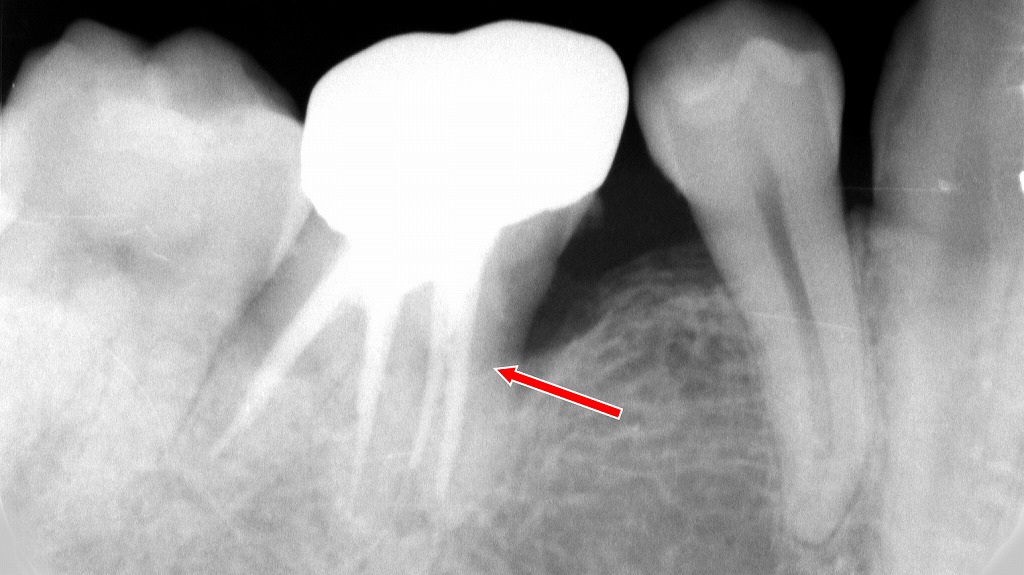

このX線画像では、大臼歯(奥歯)に複数の根管がしっかりと根尖近くまで緻密に充填されており、根管治療は適切に行われていることが確認できます。

根管充填材が根の先端まで均一に伸びており、技術的には良好な治療結果です。

■ 根管治療が奥歯で失敗しやすい主な理由

大臼歯には 2〜4 根管以上ある場合が多く、細く曲がった枝状の根管が奥深くまで広がっています。こうした複雑な形態のため、感染源を十分に取り除けないまま残ってしまうことがあり、根管治療が失敗しやすい要因になります。この画像では、強く湾曲した根管と根尖病巣が確認でき、治療の難易度が高いことを示しています。

① 根管が複雑で清掃が不十分になりやすい

大臼歯は 2〜4根管以上あることも多く、細く曲がった枝状の根管が存在します。完全な清掃・消毒が十分届かない部分が残ると、細菌が生き残り、根尖に炎症が残ります。